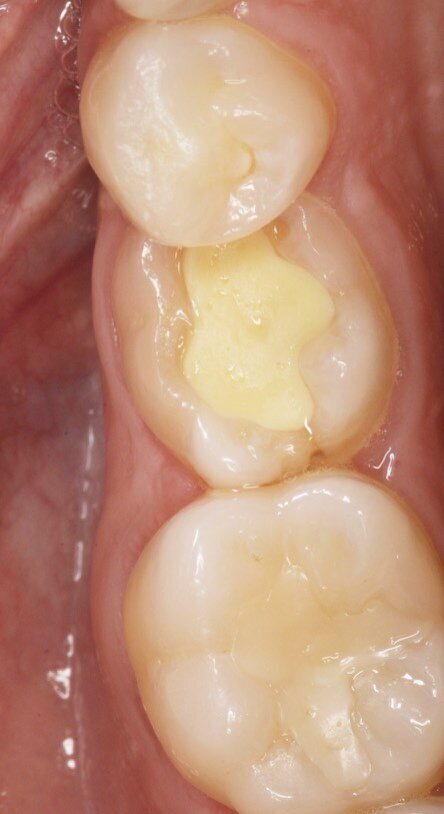

Fig. 1_In evidenza la persistenza dei decidui in quadrante 3-4.

Fig. 2_Visualizzazione occlusale sx.

Fig. 3_Visualizzazione occlusale dx.

Fig. 4_L’arcata inferiore.